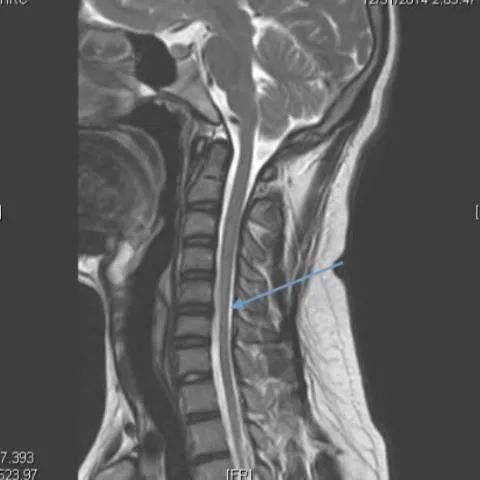

颈椎核磁共振在这种罕见疾病的诊断中起着重要的作用。矢状位磁共振成像显示细微的局灶性颈髓萎缩(图2 & 3),尤其是在下颈部。屈曲位成像示硬脑膜的前移位,后硬膜外腔增宽(图4)和更明显的脊髓变细,这在中立位不明显(图5)。

平山病是一种青少年型脊髓性肌萎缩症,其特征是手和前臂肌肉(C7-T1肌节)的单侧或不对称双侧受累。这种非进行性局灶性肌萎缩主要影响生命第二个十年的男性。感觉系统和肱桡肌的相对保留是这种肌萎缩的特征。虽然确切的机制尚不确定,但一些人认为脊柱和椎管内容物的不相称增长是短而紧的硬膜囊的原因,导致屈曲时脊髓受压。这一慢性过程导致脊髓前动脉区域的微循环障碍。中立位的MRI发现包括颈椎前凸丧失、局部脊髓变细或变平以及极少的髓内信号变化。屈曲位成像显示硬脑膜向前移位,导致后部硬膜外腔扩大。对比磁共振成像显示新月形强化硬膜外腔。颈椎在中立位和屈曲位的动态磁共振成像在诊断中是很重要的,尤其是在有典型临床表现的患者中。早期诊断是必不可少的,因为早期应用颈圈可以降低这种疾病的发病率。